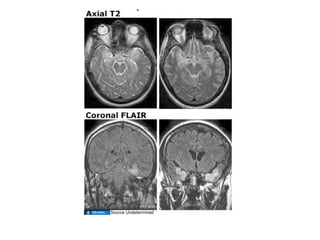

78 year old female was brought to the emergency room

by her daughter because of confusion. Over the past

week the patient has been progressively forgetful, but

it was thought by the family just to be normal Alzheimer s .

However, the past 2 days she has had low grade fevers,

mild headache, and has been hallucinating and complaining

of strange smells. In the ER she has a generalized seizure.

On exam she has a low grade temperature (38.1°C), her

vital signs are stable, but she is postictal and minimally

responsiveness. CSF exam shows 350 WBCs (90%

mononuclear), 2,500 RBCs, normal glucose, and elevated

protein (100 mg/dL). Non-contrast head CT is negative.

MRI is obtained.

Diagnosis?

–    MRI helpful if positive but not specific for HSV